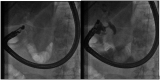

Introduction: The minimally invasive approach of endoscopic ultrasound (EUS)-guided procedures for cholecystocholedocholithiasis, such as EUS-guided gallbladder drainage (EUS-GBD), EUS-guided rendezvous (EUS-RV), and EUS-guided biliary drainage (EUS-BD), is affirmed as an effective treatment for patients with acute cholecystitis (AC) who are unfit for surgery and for patients with common bile duct stones (CBDSs) who have experienced a previous ERCP failure. Furthermore, in cases of difficult CBDS extraction during endoscopic retrograde cholangiopancreatography (ERCP), cholangioscopy-guided electrohydraulic lithotripsy (CS-EHL) has showed optimal results. The main objective of our study was to evaluate the effectiveness of EUS-GBD and percutaneous gallbladder drainage (PT-GBD) in patients with AC who are unfit for surgery. We also aimed to evaluate the efficacy of EUS-GBD, EUS-BD, and EUS-RV following ERCP failure and the effectiveness of CS-EHL for difficult CBDS extraction in our hospital. The secondary aim was to examine the safety of these procedures.

Materials and methods: We conducted a retrospective evaluation of all the EUS-GBD, PT-GBD, EUS-BD, EUS-RV, and CS-EHL procedures, which were prospectively collected in the gastroenterology and digestive endoscopy unit and the general surgery unit from January 2020 to June 2023. The efficacy was expressed in terms of technical and clinical success rates, while safety was assessed based on the rate of adverse events (AEs).

Results: We enrolled 83 patients with AC and high surgical risk. Among them, 57 patients (68.7%, 24/57 male, median age 85 ± 11 years) underwent EUS-GBD, and 26 (31.3%, 19/26 male, median age 83 ± 7 years) underwent PT-GBD. The technical and clinical success rates were 96.5 and 100% for EUS-GBD, and 96.1 and 92% for PT-GBD. The AEs for EUS-GBD were 1.7%, and for PT-GBD, it was 12%. ERCP for CBDS extraction failed in 77 patients. Among them, 73 patients (94.8%) underwent EUS-RV with technical and clinical success rates of 72.6% (53/73) and 100%, respectively. No AEs were reported. Four out of 77 patients were directly treated with EUS-BD for pyloric inflammatory stenosis. In 12 patients (16.4%), following unsuccessful EUS-RV with a CBD diameter ≥ 12 mm, an EUS-BD was performed. Both technical and clinical success rates for EUS-BD were 100%, and no AEs were reported. EUS-GBD was the treatment of choice for the remaining 8 (10.9%) patients after failure of both ERCP and EUS-RV. The procedure had high technical and clinical success rates (both at 100%), and no AEs were reported. The 12 difficult CBDS extraction treated with CS-EHL also showed high technical and clinical success rates (both at 100%), with no reported AEs.